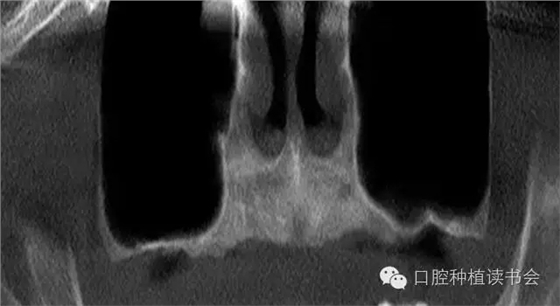

上頜竇氣化的現(xiàn)象主要來(lái)自先天因素和生理病理性因素,有的病人雖然年輕,但上頜竇腔較大,后牙牙根幾乎伸進(jìn)上頜竇。隨著年齡增大、磨牙缺失,由于上頜竇處于負(fù)壓狀態(tài),尤其是缺牙后缺少來(lái)自牙槽脊的功能刺激,氣化現(xiàn)象會(huì)更嚴(yán)重,加之原有竇腔較大,就表現(xiàn)為巨大的上頜竇腔,甚至竇底與鼻底在同一水平(圖2)。有研究表明,上頜竇容積在青少年階段隨年齡而變化,中老年階段達(dá)到穩(wěn)定狀態(tài),氣化系數(shù)無(wú)增齡性改變。上頜竇竇腔平均最大容積為:38*33*38mm(Chih-Long,2014)。上頜竇容積和牙槽骨骨量呈負(fù)相關(guān),上頜牙全部脫落促進(jìn)上頜竇變形,上頜竇容積有減小趨勢(shì)。上頜骨的老化特點(diǎn)是一個(gè)漸變的過(guò)程,步入中年期開(kāi)始進(jìn)行重塑,而老年期上頜骨形態(tài)變化較小。